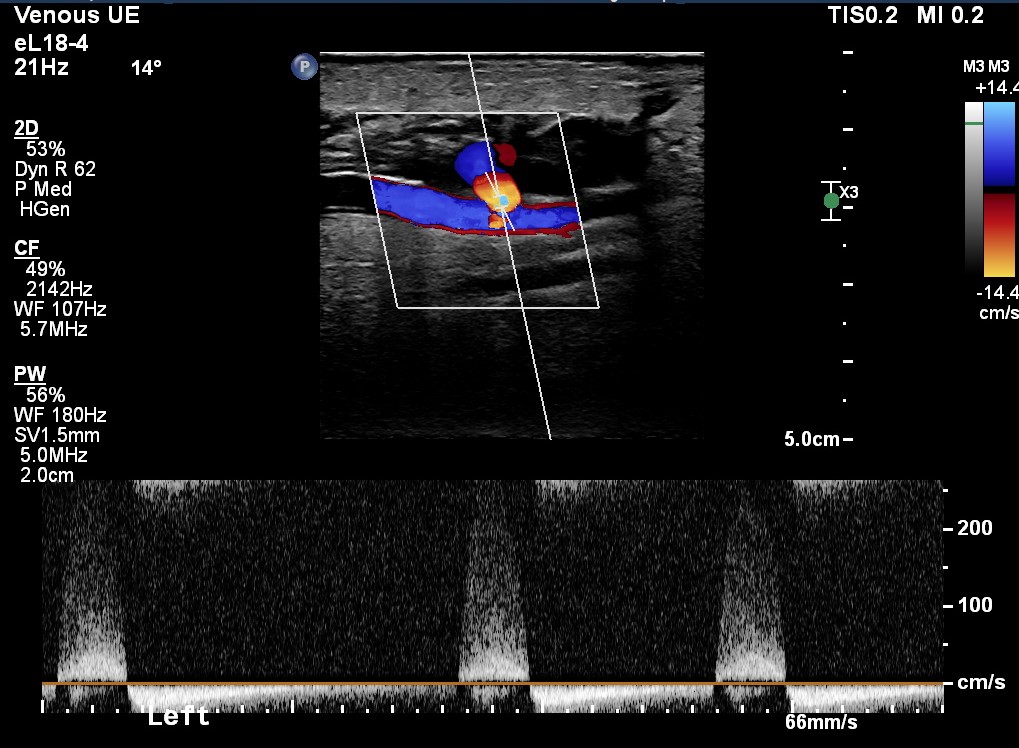

Figure 2 - Demonstrates the findings with Colour Doppler which demonstrate a "yin-yang sign" of swirling blood flow in a small portion of the cystic structure and also the location of the brachial artery deep to this.

Figure 3 - Demonstrates the Spectral Doppler trace, this has a "to and fro" waveform.